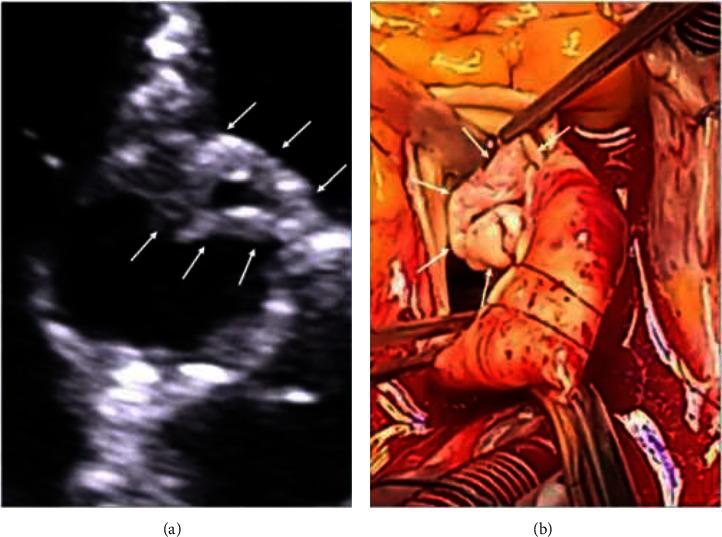

Broviac catheter is a type of central venous catheter (CVC) used for long-term parenteral nutrition in specific patients, e.g., diagnosed with intestinal failure as short bowel syndrome (SBS). The way of the catheter insertion is conceived to minimalize the risk of infections. However, CVC-related blood stream infections (CVC-BSIs), including infective endocarditis (IE), remain most important complications associated with Broviac catheter. stands out as a prevalent pathogen. The increasing number of CVCs results in an increased incidence of healthcare-associated IE. Complete parenteral treatment is an independent risk that increases the likelihood of IE. Treatment of IE is mainly based on antibiotic therapy, but in certain cases, surgical treatment is needed. A 71-year-old female with SBS who had been receiving total parenteral nutrition through the Broviac catheter for several months was admitted in a serious condition with significant weakness, increasing shortness of breath, deteriorating cough, fever, low blood pressure, and heart palpitations. Echocardiography revealed severe aortic valve IE with a large, longitudinal, highly mobile vegetation (up to 40 mm) and massive aortic regurgitation with pulmonary edema. Fast pathogen detection in the patients' blood () was obtained using PCR-based multiplex test. Due to life-threatening conditions, emergency surgery with aortic valve replacement was performed. Consistent rehabilitation resulted in good condition achievement. Follow-up echocardiography showed normal function of the aortic valve bioprosthesis. The use of CVC, including Broviac catheter, is associated with an increased risk of infections, including IE. Treatment-resistant severe HF complicating IE requires emergency surgery.

布罗维阿克导管是一种中心静脉导管(CVC),用于特定患者的长期肠外营养,例如,被诊断为短肠综合征(SBS)导致肠衰竭的患者。导管插入方式旨在将感染风险降至最低。然而,与中心静脉导管相关的血流感染(CVC-BSIs),包括感染性心内膜炎(IE),仍然是与布罗维阿克导管相关的最重要并发症。 是一种常见病原体。中心静脉导管数量的增加导致医疗相关感染性心内膜炎的发病率上升。完全肠外治疗是增加感染性心内膜炎可能性的独立风险因素。感染性心内膜炎的治疗主要基于抗生素治疗,但在某些情况下,需要进行手术治疗。 一名71岁患有短肠综合征的女性,通过布罗维阿克导管接受了数月的全肠外营养,因病情严重入院,伴有明显虚弱、呼吸急促加重、咳嗽恶化、发热、低血压和心悸。超声心动图显示严重的主动脉瓣感染性心内膜炎,伴有一个大的、纵向的、高度活动的赘生物(长达40毫米)以及大量主动脉瓣反流伴肺水肿。使用基于聚合酶链反应的多重检测方法对患者血液进行快速病原体检测。由于病情危及生命,进行了主动脉瓣置换的急诊手术。持续的康复治疗使病情好转。随访超声心动图显示主动脉瓣生物假体功能正常。 使用包括布罗维阿克导管在内的中心静脉导管会增加包括感染性心内膜炎在内的感染风险。并发感染性心内膜炎的难治性严重心力衰竭需要急诊手术。